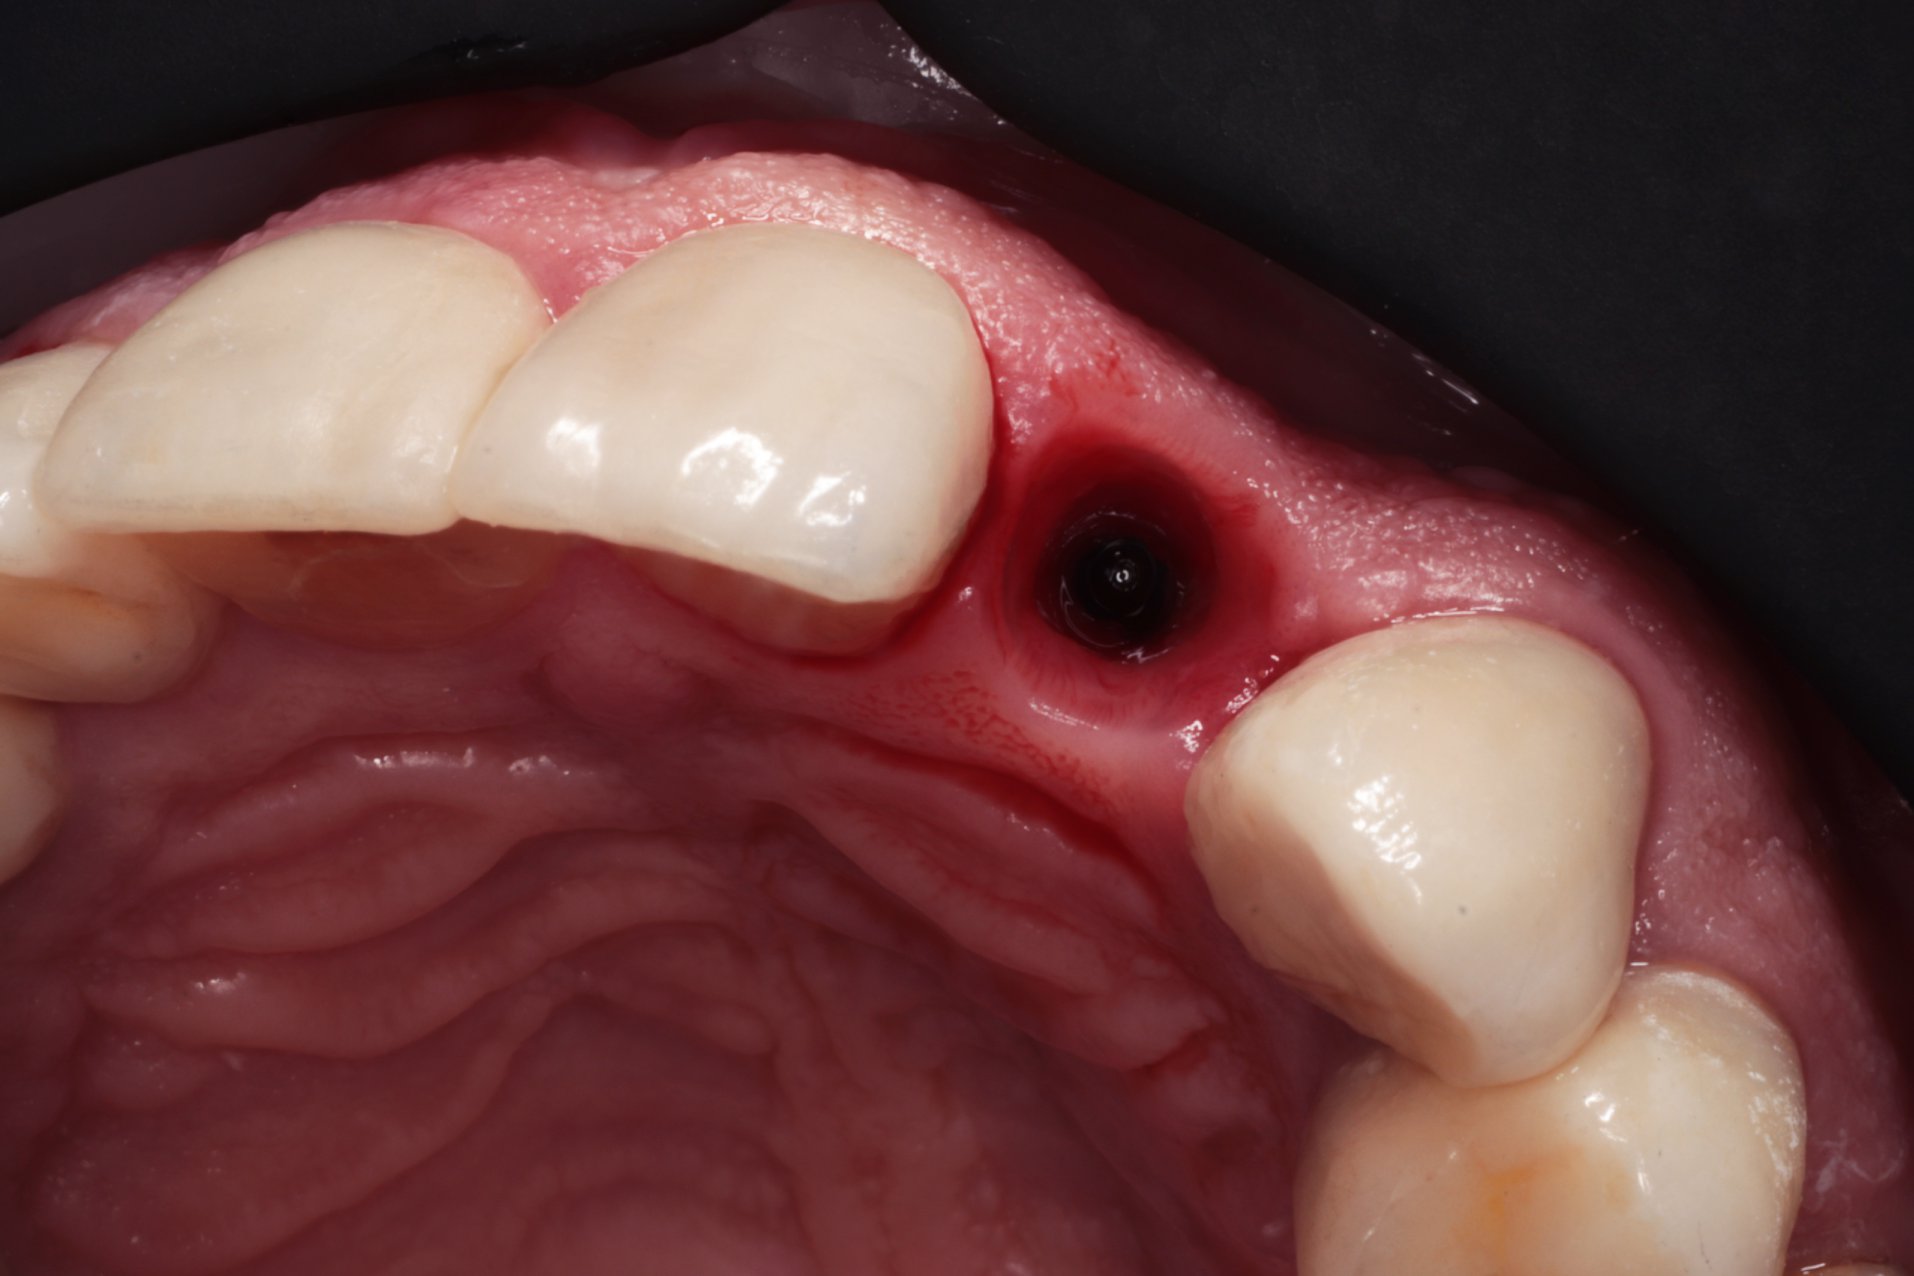

Są sytuacje, w których utrata zęba zwłaszcza w odcinku przednim jest paraliżująca i ograniczająca nasze stosunki międzyludzkie. Współczesna stomatologia zna rozwiązania, które mogą takie sytuacje deprymujące każdego człowieka rozwiązać. Zaopatrzenie bezzębnego wyrostka w odcinku przednim może mieć różny charakter i różną formę. Korona tymczasowa kompozytowa obciążająca implant – to korona zintegrowana z filarem protetycznym. Dzięki odpowiednio opracowanemu profilowi wyłaniania niewątpliwą korzyścią jest kształtowanie dziąsła pod ostateczną koronę cyrkonową na filarze indywidualnym typu „Atlantis”. Fakt, że pacjent może się posługiwać zębem, który jest stabilnie przykręcony do implantu i jednocześnie kształtujący brodawki międzyzębowe oraz dziąsło otaczające implant jest bardzo ważnym elementem w planowaniu leczenia implanto-protetycznego.